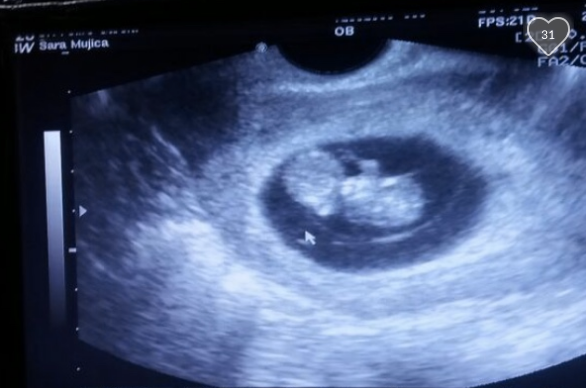

Mujica is now 12 weeks pregnant. She and her fiancée, Victor Cruz, 19, have decided to keep the baby and are trying to raise funds for the baby's health care, however cyber critics' attacks have been running rampant on her GoFundMe page.

Photo: Sara Mujica Facebook